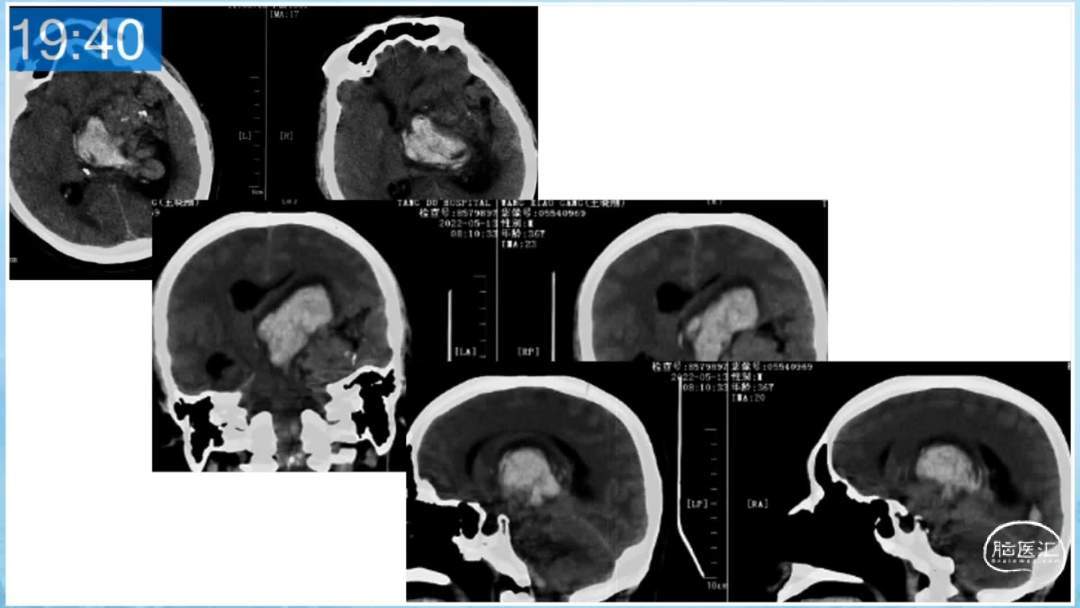

本期为大家特别分享:空军军医大学唐都医院邓剑平教授的精彩会议内容《颅内动静脉畸形的复合手术治疗》,欢迎大家阅读和分享!